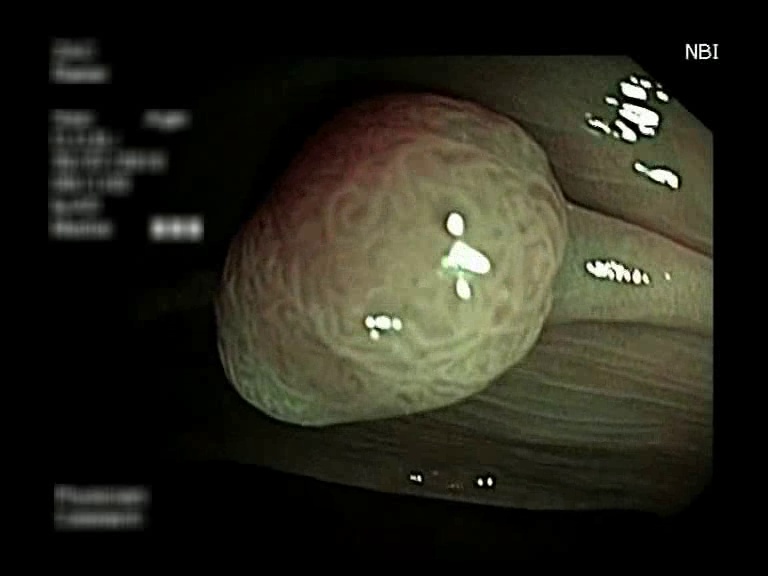

Figure 3: Key-frames obtained by our method and their corresponding depth maps. The polyp is visible from different viewing angles in these selected frames.

The selected key-frames are finally used to reconstruct the 3D surface of the polyp. We have used Facebook’s 3D image GUI to view the reconstructed polyp surface, the link to the video is shown here: https://youtu.be/PJKfk0Mqu2I\href https://youtu.be/PJKfk0Mqu2I. 3D visualization of a polyp helps in surgeries involving the removal of the polyp from its root. This gives better visualization of polyps for diagnosis. Fig. 3 shows some of the results of key-frame extraction and the corresponding depth maps. No publicly available datasets or methods using them that predict depth maps from endoscopic frames exist. Thus, a comparison between different methods for predicting depth from endoscopic images couldn’t be performed.